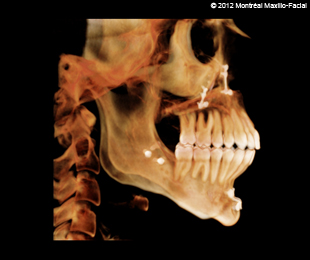

- Photos & radiographies